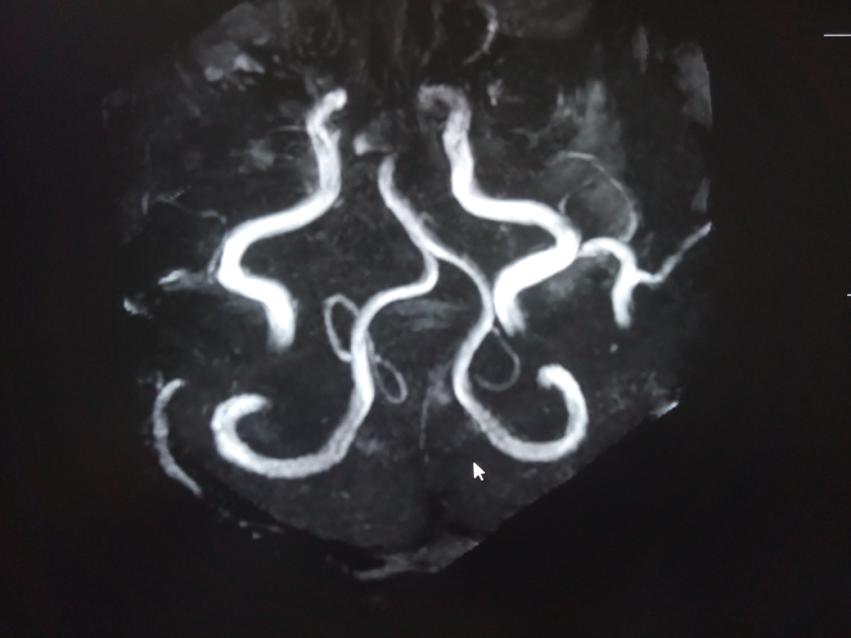

舌咽神经MRTA检查发现同侧椎动脉及小脑后下动脉压迫舌咽及迷走神经